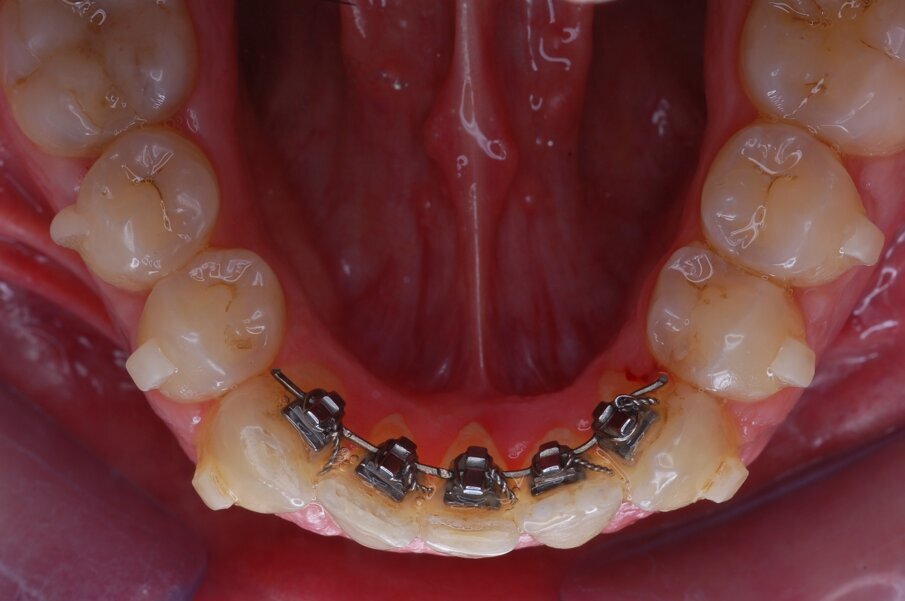

Diagnosi ed eziologia Un uomo sano di 39 anni si è presentato nel nostro studio ortodontico lamentando un aspetto dentale poco attraente e la paura della chirurgia ortognatica proposta da un altro ortodontista. Clinicamente, il profilo del paziente era rettilineo e la vista frontale non mostrava alcuna asimmetria facciale. L’esame funzionale non ha rivelato alcuna deviazione mandibolare o riduzione dei movimenti. Il paziente non aveva dolori articolari e non sono stati rilevati rumori articolari. Era presente una lieve occlusione molare bilaterale di Classe II, un morso aperto e un grave affollamento in entrambe le arcate. L’affollamento era particolarmente grave nell’arcata mandibolare, sebbene mancasse l’incisivo centrale mandibolare destro. Gli incisivi mascellari erano di piccole dimensioni, suggerendo una discrepanza dell’indice di Bolton se fossero stati presenti tutti e quattro gli incisivi mandibolari. Erano inoltre presenti un morso incrociato nella regione dell’incisivo laterale superiore sinistro e una grave rotazione distale del secondo premolare mandibolare sinistro (Figg. 1-8).

Figg. 1-8_Fotografie facciali e intraorali pre-trattamento.